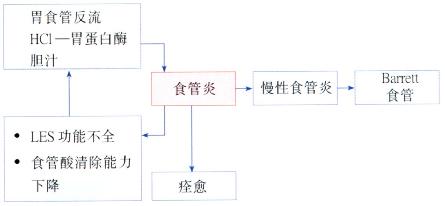

【并发症】(图3.16)

Barrett食管是慢性GERD的一种并发症。为更好地抵抗反流物的损伤,食管远端的正常鳞状上皮被化生的柱状上皮所取代(图3.17)。

图3.16食管炎的病理生理变化。

图3.17Barrett食管。

Barrett粘膜的发生有二个重要成因:

1 食管鳞状上皮受损

2 上皮修复时食管内环境异常。

这些又可能与下列有关:

. 慢性反流性食管炎

. 十二指肠胃食管反流

. 酸清除能力减弱与以上任一因素共同存在。